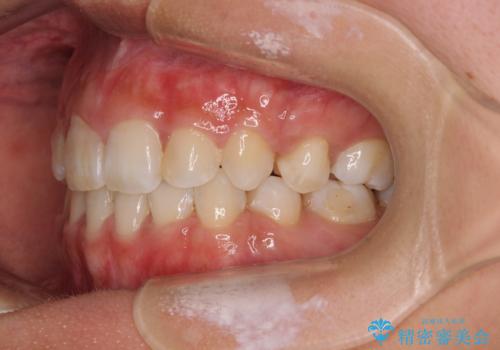

- ハーフリンガル

- 八重歯や前歯のデコボコを気にして来院された患者様です。

目立たない装置を希望されたので、上顎が裏側装置のハーフリンガルを選択し、上下左右の小臼歯(計4歯)を抜歯して矯正治療を行うこととしました。

裏側装置での矯正治療は、上顎前歯の正中のズレをまっすぐに改善することが難しいのですが、きれいに整えることができました。

補助装置を用いて抜歯したスペースを速やかに閉じたことで、短期間での治療となりました。